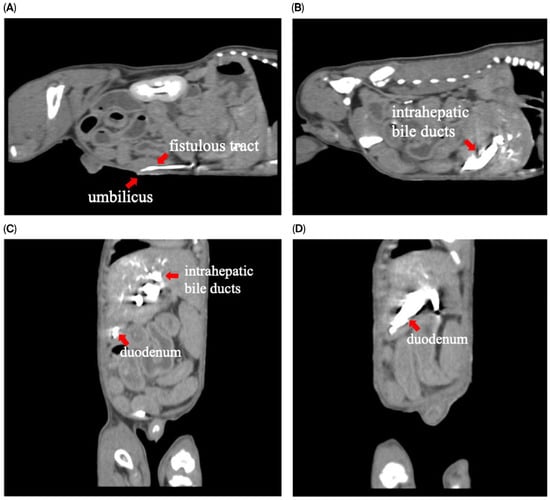

Concurrent Congenital Umbilicobiliary Fistula and Vesicourachal Diverticula in a Dog

Congenital umbilicobiliary fistula is a rare disease reported in humans and dogs. A 2-month-old, intact, male French Bulldog presented with a greenish-yellow discharge dripping from the umbilicus since birth. Complete blood count and serum biochemistry were within normal limits, but serum alkaline phosphatase [...] Read more.

Congenital umbilicobiliary fistula is a rare disease reported in humans and dogs. A 2-month-old, intact, male French Bulldog presented with a greenish-yellow discharge dripping from the umbilicus since birth. Complete blood count and serum biochemistry were within normal limits, but serum alkaline phosphatase activity was mildly elevated. A positive contrast cystogram was performed to rule out a patent urachus and confirmed the presence of a vesicourachal diverticula, a type of urachal anomalies. An abdominal ultrasound and computed tomography fistulogram demonstrated a communication between the umbilicus and common bile duct, which suggested an umbilicobiliary fistula. Surgical correction of the umbilicobiliary fistula and vesicourachal diverticula was successfully performed with an uneventful recovery. Histological analysis of the fistulous tract demonstrated a cuboidal/columnar lining epithelium that transitioned to squamous epithelium near the umbilicus. Agenesis of the gallbladder was noted. The application of multiple imaging techniques in the diagnosis and surgical correction of these congenital abnormalities (umbilicobiliary fistula, gallbladder agenesis, and vesicourachal diverticula) was beneficial for treatment planning and outcome. Full article